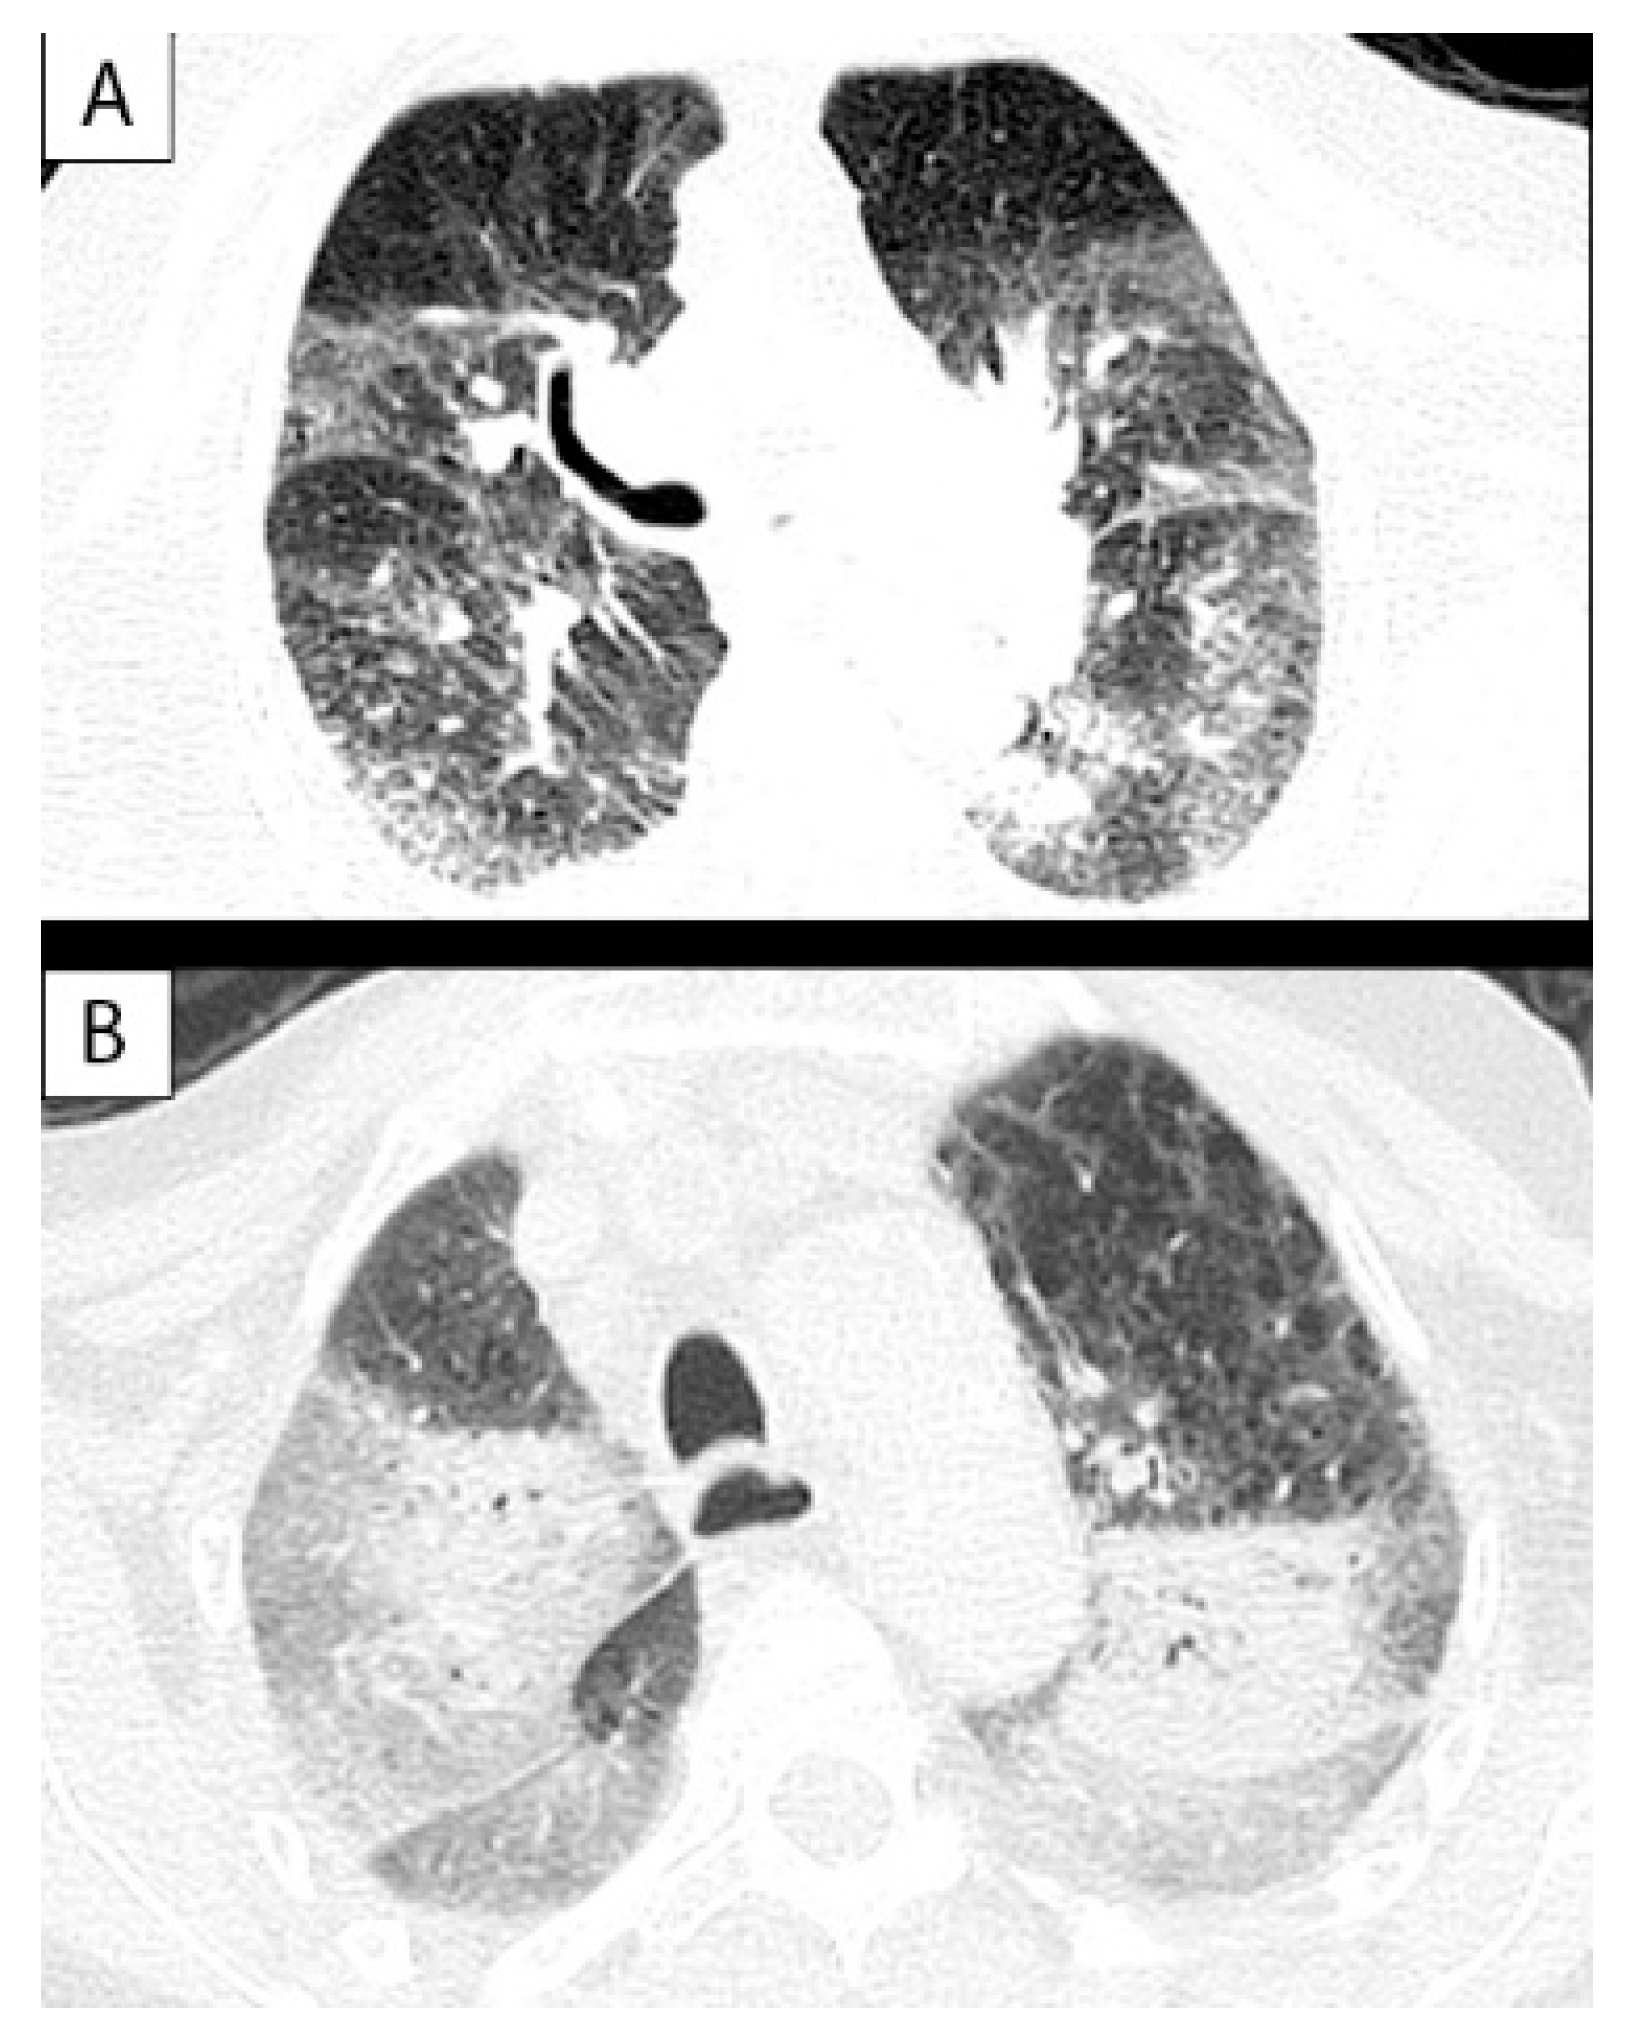

| CT Finding | Case 1 | Case 2 | Case 3 | Case 4 | Case 5 | Case 6 | Case 7 | Case 8 | Case 9 |

|---|---|---|---|---|---|---|---|---|---|

| Ground glass opacities | x | x | x | x | x | x | x | x | x |

| -Peripheral | x | ||||||||

| -Bilateral | x | x | x | x | x | x | x | x | x |

| -Multilobar | x | x | x | x | x | x | x | x | x |

| -no gravitational distribution | x | x | x | x | |||||

| “Crazy paving” pattern | x | ||||||||

| Alveolar consolidations | x | x | x | x | |||||

| Lymphadenopathies | x | ||||||||

| Pleural effusion | x | x | x | x | x | x | x | x |